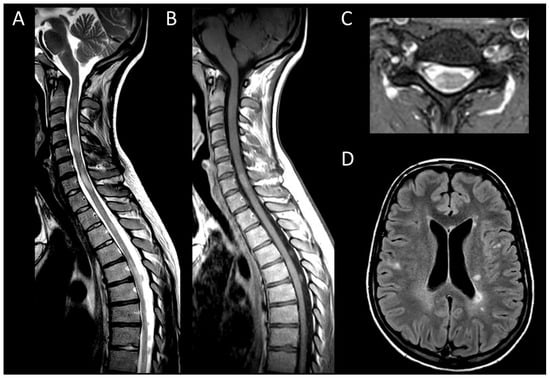

Neuromyelitis Optica Spectrum Disorders Positive for Aquaporin-4 IgG

Myelin-Oligodendrocyte Glycoprotein Antibody Associated Disease

Neurosarcoidosis